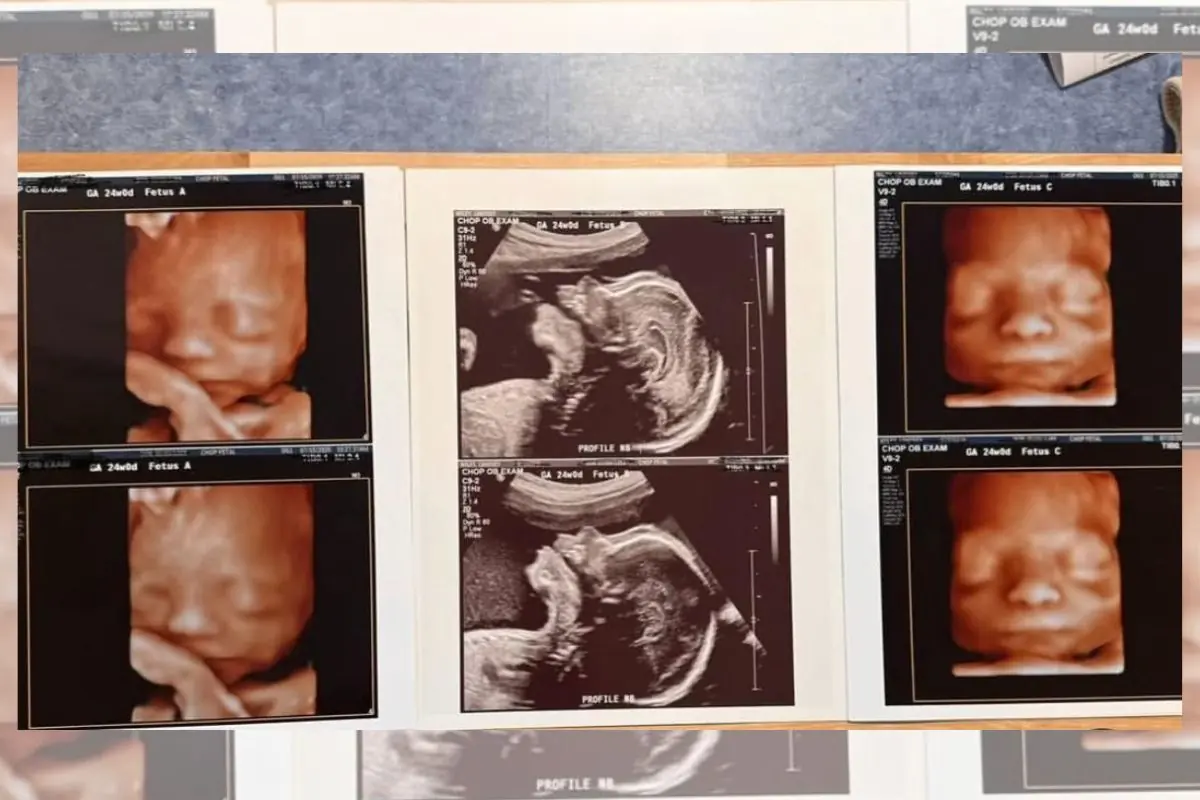

A gestante, identificada como Lindsey Wiley, de 32 anos, já era mãe de três meninos de 5, 3 e 1 ano e meio. O plano era simples: um quarto filho, quem sabe uma menina, e encerrar a fase das gestações. Porém, na primeira ultrassonografia desta gestação, o susto veio em dose tripla.

Segundo relatos, o impacto do diagnóstico foi imediato. “De primeira, fiquei chocada e com medo”, confessou Lindsey à imprensa. A notícia de que viria uma menina trouxe esperança — o resultado surpreendeu. Em vez de um bebê, seriam três vidas novas para cuidar de uma só vez.